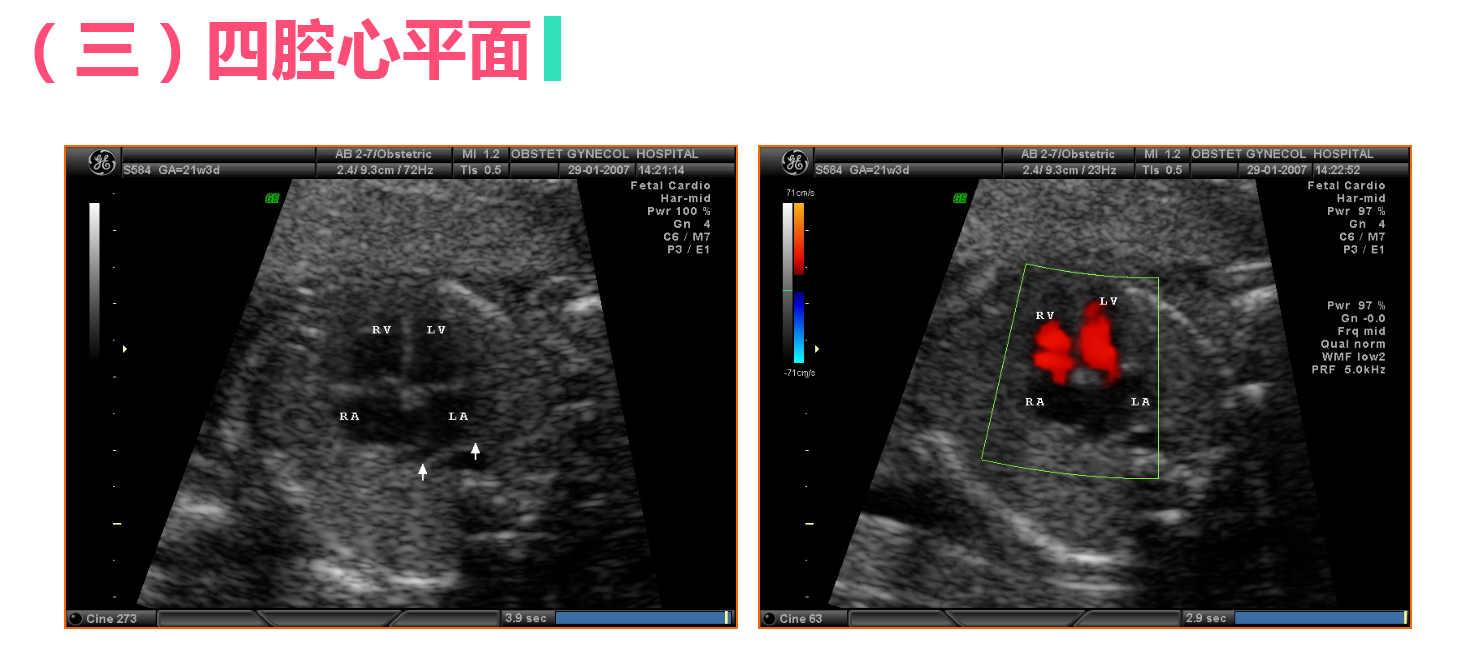

• 4.3 正常中晚期妊娠声像图

正常中晚期妊娠声像图